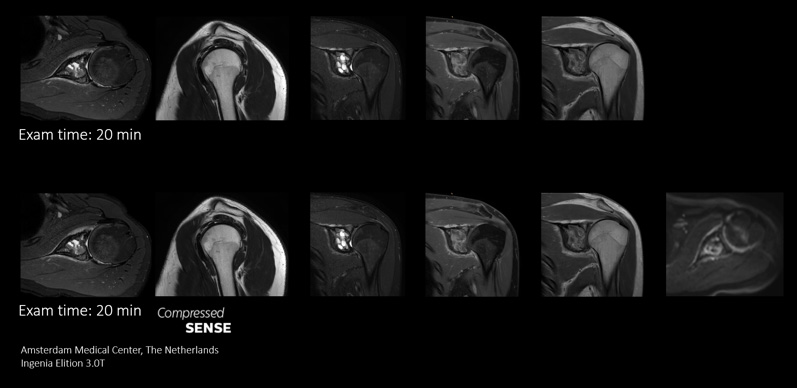

In conventional MRI scan techniques, high resolution imaging can involve long scan times which may be difficult for patients experiencing pain and discomfort. Long scan times can also make it difficult to fit high resolution imaging into acceptable MRI scan time slots for busy departments. Compressed SENSE enables fast 3D submillimeter (0.7 mm or less) isotropic images in less than 5 minutes to help diagnose challenging patients and anatomies.